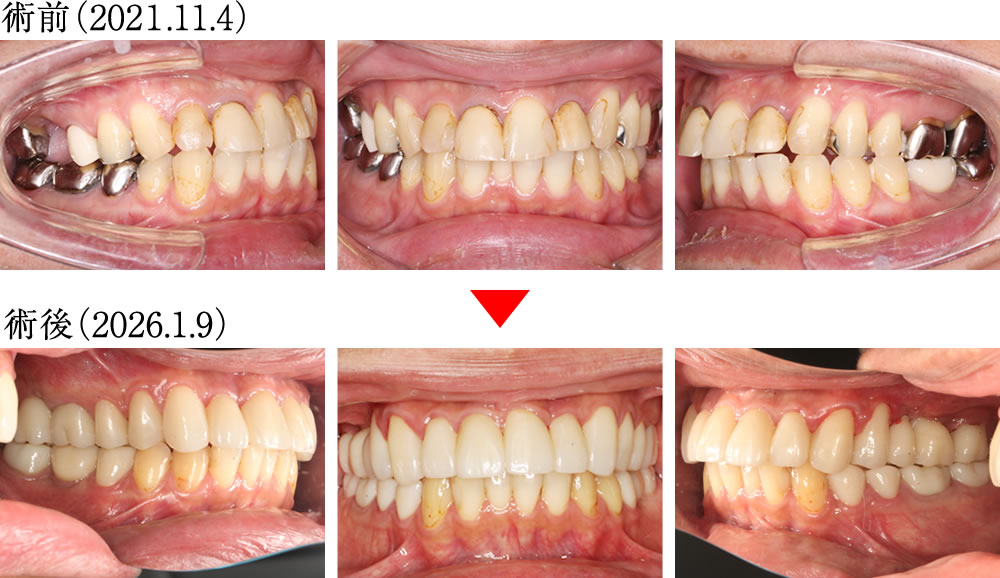

インプラントとセラミック治療で咬み合わせ・見た目を改善した症例

こちらの患者さまは、保存不可能な歯を抜歯後にインプラント治療を行い、古い金属の詰め物や被せ物は、ジルコニアセラミックにて治療する計画を立てました。

術前は、上下顎ともに古いつめ物が多く、咬み合わせも不安定な状態でした。術後は、精度と審美性に優れたセラミック修復により、自然で美しい口元へと改善しました。

歯並び・咬み合わせの比較

術前は、古いつめ物やかぶせ物の影響により、歯並びや咬み合わせが乱れている状態でした。術後は、歯並びと咬み合わせが整い、理想的で美しい口元になりました。

| 年齢・性別 | 40代 男性 |

| 治療期間 | 約1年 |

| 治療回数 | 約30回 |

| 治療費 | 2,436,500円(税込) (インプラント880,000円(税込)を含む、上部ジルコニア補綴) |